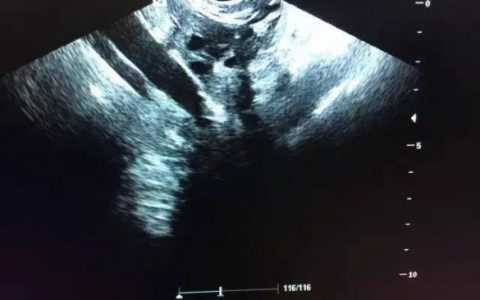

陈寸,三亚市妇幼保健院超声科主治医师,毕业于郑州大学临床医学系,从事超声工作十余年,系海南省医学会超声专业委员会委员。2014年于广州市妇女儿童医疗中心妇产科超声及儿科超声进修半年;2026年于中山大学附属第一医院妇产超声科进修半年。获得《......